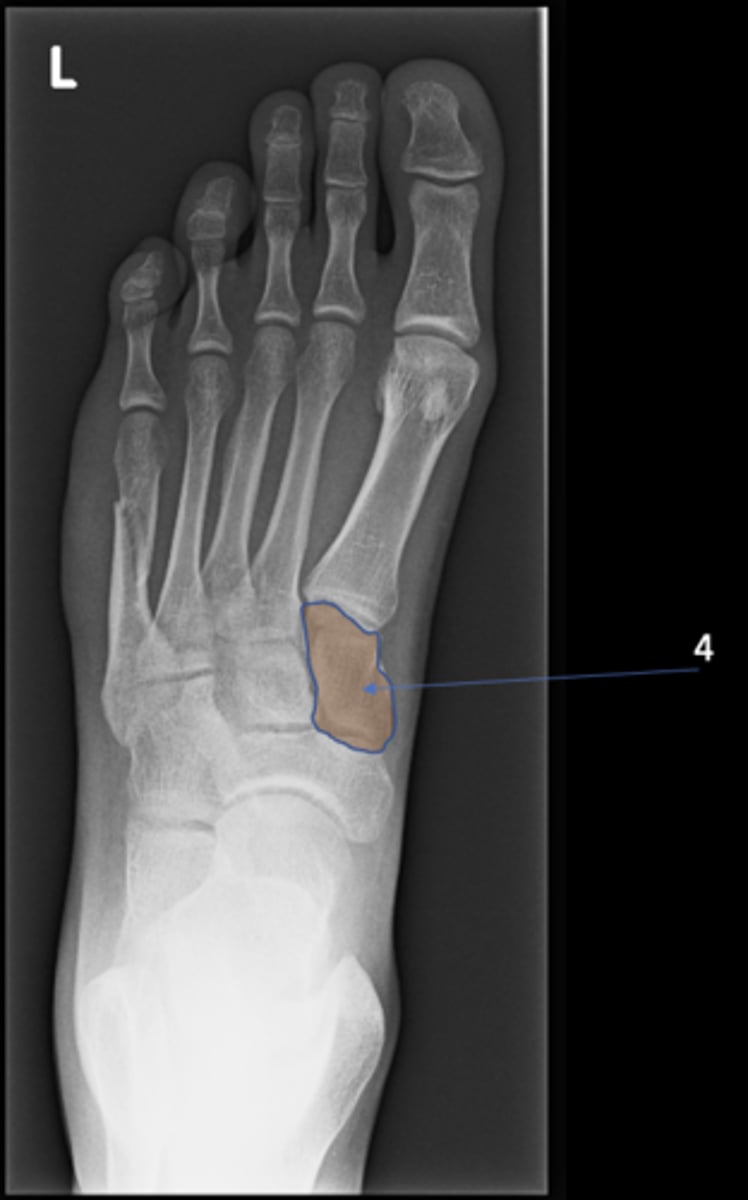

New cards

Left inferior pubic ramus

ID 15

<p>ID 15</p>

15

S1 tubercle

ID 16

<p>ID 16</p>

16